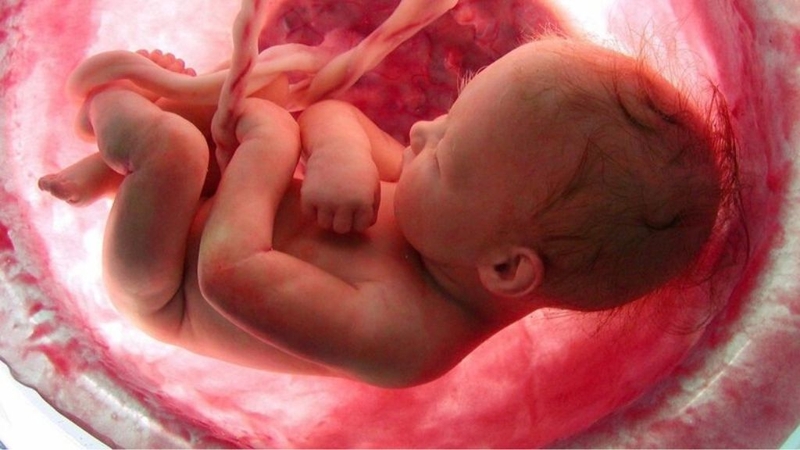

Siêu âm là kỹ thuật hình ảnh có sử dụng sóng âm thanh để tạo ra hình ảnh rõ ràng nhất của thai nhi nằm trong tử cung. Qua hình ảnh này, bác sĩ sẽ chẩn đoán sự tăng trưởng và phát triển của em bé cũng như theo dõi sức khoẻ của thai phụ. Vậy nên có thể thấy siêu âm thai sẽ là cách để tầm soát hiệu quả các vấn đề xảy ra trong quá trình mang thai.

Nhiều mẹ bầu thường cho rằng siêu âm thời điểm nào cũng được tuy nhiên đây là suy nghĩ rất nguy hiểm. Có những dạng dị tật chỉ được phát hiện qua siêu âm vào một thời điểm nhất định của thai kỳ, đây là một trong những phương pháp “sàng lọc dị tật” rất nên làm từ những tuần thai đầu để bảo vệ sức khoẻ cả mẹ và bé. Sau đây là 3 mốc siêu âm thai nhi quan trọng nhất mà mẹ bầu cần nắm:

Lúc này là thời điểm có thể đo được độ mờ da gáy, dự đoán sự bất thường về nhiễm sắc thể nguy hiểm từ đó ngừa được bệnh down, dị dạng tim, các chi. Điều quan trọng hơn mà mẹ bầu cần nắm là chỉ có thời điểm này mới đo được độ mờ da gáy, bước sang tuần thứ 13 thì các giá trị siêu âm không còn chính xác.

Siêu âm thai lúc này để bác sĩ quan sát được tất cả những bất thường về hình thái của thai nhi như sứt môi, hở hàm ếch, dị tật các cơ quan và nội tạng. Đặc biệt siêu âm này phải được thực hiện muộn nhất là trước tuần thứ 28 và mẹ bầu cần tìm đến cơ sở thăm khám uy tín để được bác sĩ giàu kinh nghiệm siêu âm.

Đây được xem là lần siêu âm “chốt” trước khi sinh nên bà bầu không được chủ quan bỏ qua. Có những vấn đề về sức khỏe sẽ xảy ra muộn, đó có thể là bất thường ở động mạch, tim, cấu trúc não. Ngoài ra lúc này bác sĩ sẽ tiên đoán được thời gian dự sinh, đánh giá sức khoẻ của mẹ có đủ để “vượt cạn” tự nhiên hay không và kịp thời có biện pháp can thiệp.